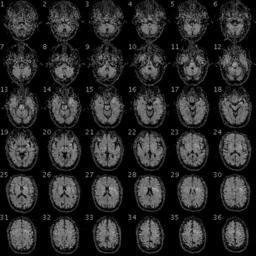

MAKE A MEME View Large Image 100325 RS88UH 11 qc.gif en fMRI of the brain/head of a PGP participant with the following data Demographic Information Date of Birth 1954-08-28 58 years old Gender Male Weight 246lbs 112kg Height 6ft 5in 195cm Blood Type O+ Race White https ...

Keywords: 100325 RS88UH 11 qc.gif en fMRI of the brain/head of a PGP participant with the following data Demographic Information Date of Birth 1954-08-28 58 years old Gender Male Weight 246lbs 112kg Height 6ft 5in 195cm Blood Type O+ Race White https //my personalgenomes org/profile/hu43860C Personal Genome Project https //my personalgenomes org/profile/hu43860C PGP Scientists 2010-04-29 cc-zero To the extent possible under law PersonalGenomes org has waived all copyright and related or neighboring rights to Personal Genome Project Participant Genetic and Trait Dataset This work is published from United States Magnetic resonance imaging Personal Genome Project